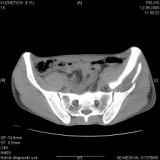

Уважаемые коллеги! Хотелось бы услышать совет по тактике лечения представлленого больного.Поступил после лечения в одном изотделений области. Травма 2,5 месяца назад. После выведенияиз шока был произведен остеосинтез перелома бедра, предплечья, до перевода к нам проводилосьвытяжение по оси шейки бедра за стержень, введенный в большой вертел. На сегодня деформацияригидна, клинически мобильности не определяется. Заранее признателен. P.S. Данный вид травм не включен в перечень "высокотехнологичных операций", направить длялечения по квотам Минздрава очень сложно.

Все-таки надо бы начать не с КТ, а с обзорного снимка таза и косых проекций впадины.

Это обзорные и косые снимки

С уважением,

Привет, Леонид. Оскольчатый высокий двухколонный перелом в такие сроки трогать не надо, т.к. это про такие переломы сказано: "кто с ножом на Ж. пойдет тот в ней и останется...".